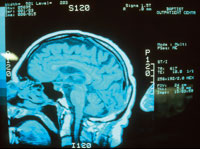

Een glasvezelverbinding maakt het mogelijk röntgenfoto's van hoge kwaliteit snel en gemakkelijk te versturen en te bekijken.